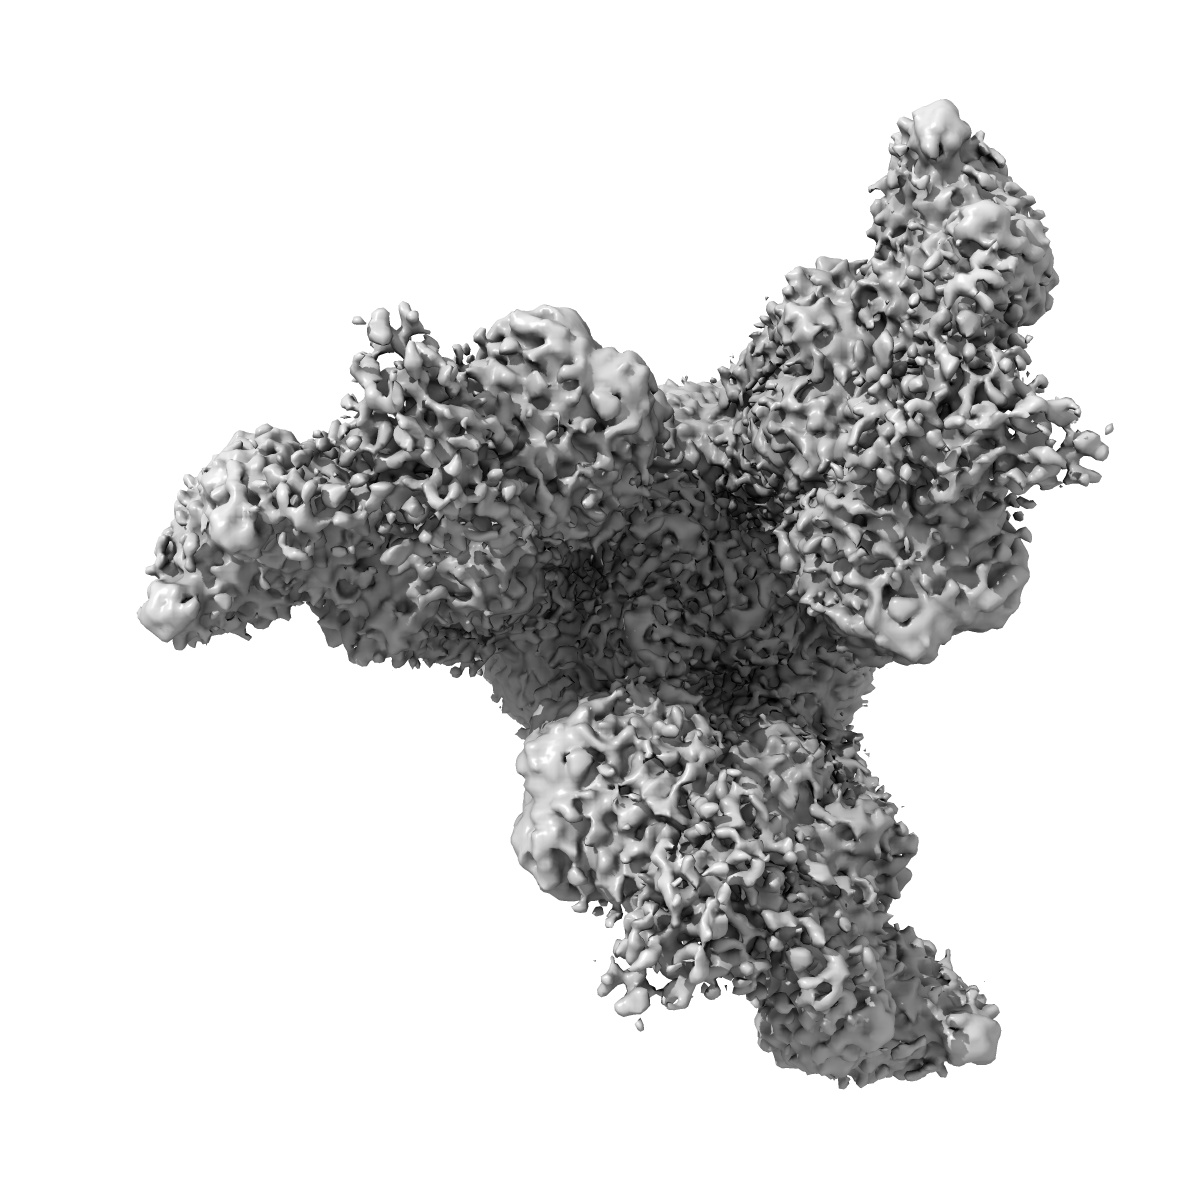

SARS-CoV-2 spike proteins trimer in complex with P17 and FC05 Fabs cocktail

EMD-30488

Single-particle

3.5 Å

Sample: SARS-CoV-2 spike proteins trimer in complex with P17 and FC05 Fabs cocktail

Fitted models: 7cwu

Structure-based development of human antibody cocktails against SARS-CoV-2.

Wang N, Sun Y , Feng R, Wang Y, Guo Y, Zhang L, Deng YQ, Wang L, Cui Z, Cao L , Zhang YJ, Li W, Zhu FC, Qin CF , Wang X

(2021) Cell Res , 31 , 101 - 103